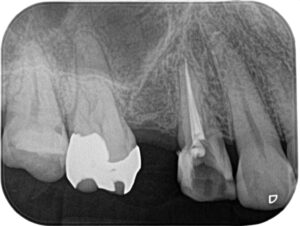

Before/After X線写真

治療前後のX線画像をご紹介します。

(画像:xray_rc1.jpg Before/After X線写真比較)

治療前には根尖周囲に淡い透過像(炎症の兆候)が見られましたが、

治療後は根管が適切に封鎖され、再感染のリスクが大きく軽減された状態が確認できます。